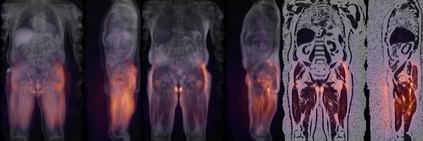

Along with rich health-related metadata, an ongoing imaging study has acquired MRI of over 40,000 male and female UK Biobank participants aged 44-82 since 2014. Phenotypes derived from these images, such as measurements of body composition, can reveal new links between genetics, cardiovascular disease, and metabolic conditions. In this retrospective study, six measurements of body composition were automatically estimated by ResNet50 neural networks for image-based regression from neck-to-knee body MRI. Despite the potential for high speed and accuracy, these networks produce no output segmentations that could indicate the reliability of individual measurements. The presented experiments therefore examine mean-variance regression and ensembling for predictive uncertainty estimation, which can quantify individual measurement errors and thereby help to identify potential outliers, anomalies, and other failure cases automatically. In 10-fold cross-validation on data of about 8,500 subjects, mean-variance regression and ensembling showed complementary benefits, reducing the mean absolute error across all predictions by 12%. Both improved the calibration of uncertainties and their ability to identify high prediction errors. With intra-class correlation coefficients (ICC) above 0.97, all targets except the liver fat content yielded relative measurement errors below 5%. Testing on another 1,000 subjects showed consistent performance, and the method was finally deployed for inference to 30,000 subjects with missing reference values. The results indicate that deep regression ensembles could ultimately provide automated, uncertainty-aware measurements of body composition for more than 120,000 UK Biobank neck-to-knee body MRI that are to be acquired within the coming years.